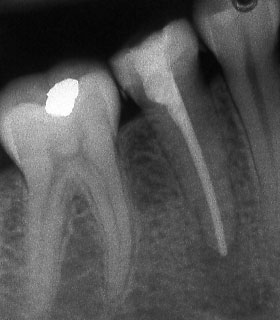

Винаги е необходимо лекуващият да се стреми към този резултат:

Понякога е налице патологичен процес около апекса на зъба, който налага да се проведе допълнителна хирургична намеса с цел отстраняване на лезията.